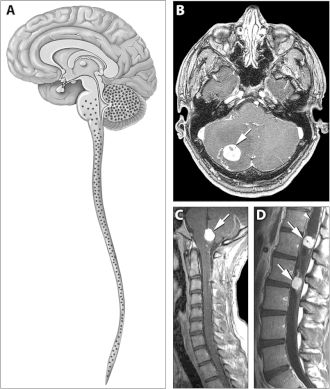

Болезнь Гиппеля — Линдау (цереброретинальный ангиоматоз, англ. Von Hippel–Lindau disease — VHL) — факоматоз, при котором гемангиобластомы мозжечка сочетаются с ангиомами спинного мозга, множественными врождёнными кистами поджелудочной железы и почек. У четверти больных развивается карцинома почки, часто первично-множественная. Симптомы заболевания становятся очевидными во 2-м десятилетии жизни — одним из первых обнаруживается кровоизлияние в глазное яблоко или в заднюю черепную ямку с признаками внутричерепной гипертензии или мозжечковыми расстройствами. У большинства пациентов в цереброспинальной жидкости обнаруживают повышение содержания белка, у половины детей с опухолями мозжечка — увеличение числа клеток.